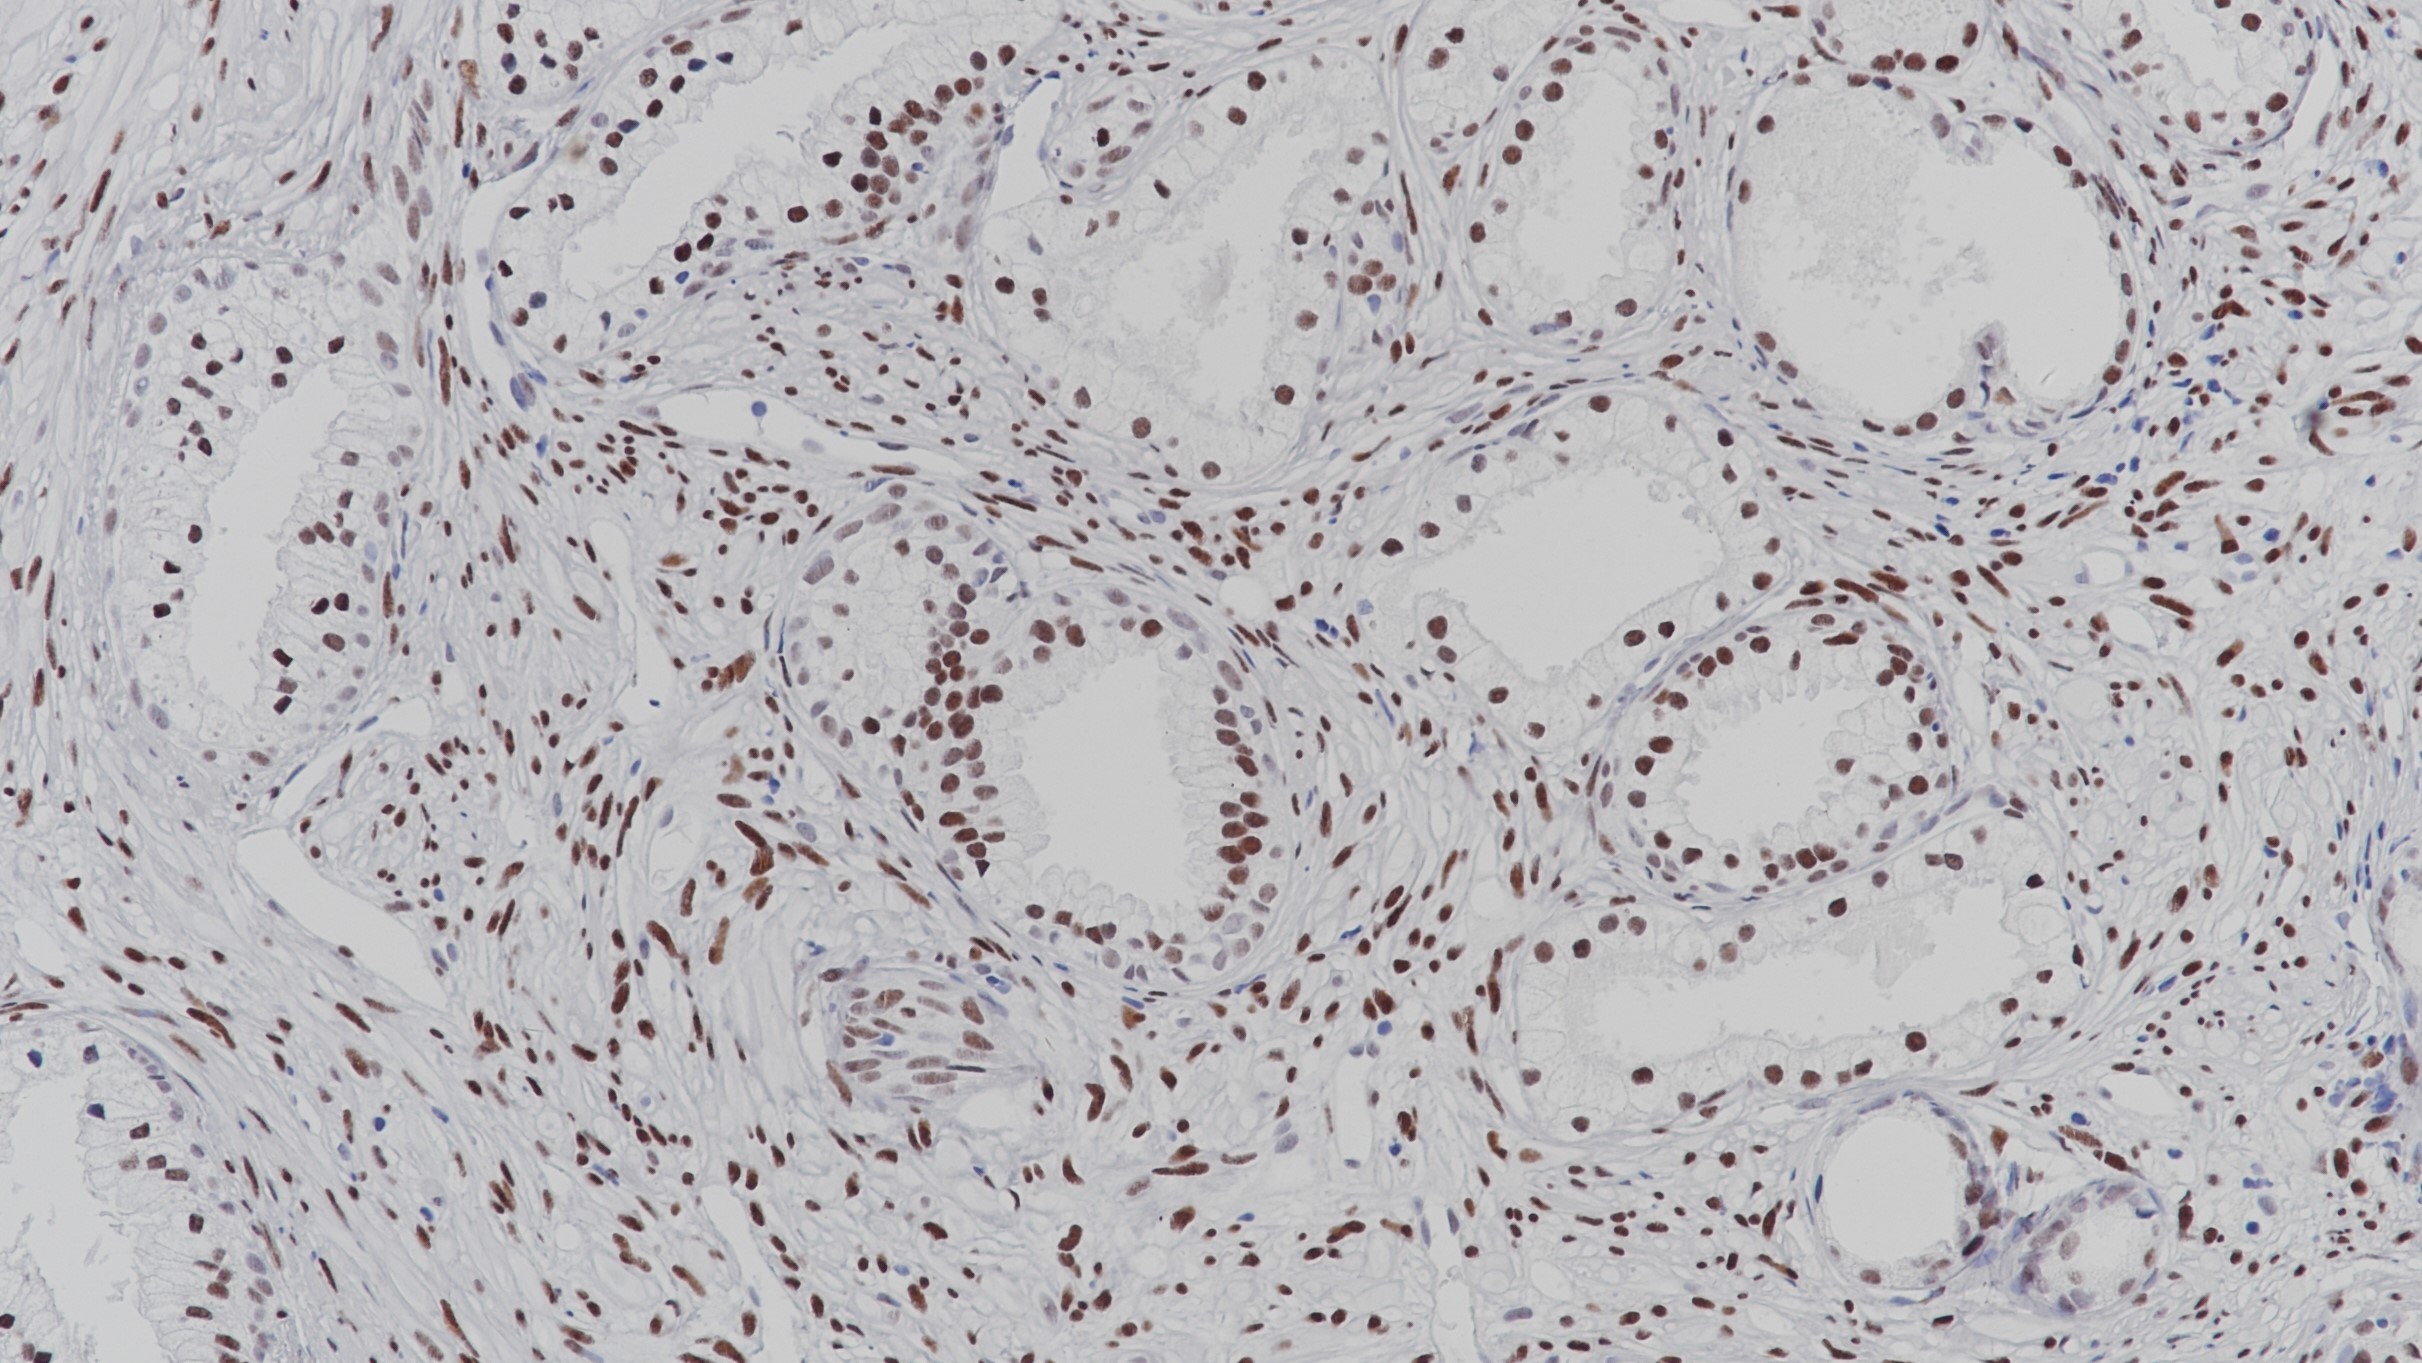

1. Liu Q , Wang G , Li Q , et al. Polycomb group proteins EZH2 and EED directly regulate androgen receptor in advanced prostate cancer.[J]. International Journal of Cancer.

2. Mckay R R, Werner L, Mostaghel E A, et al. A phase II trial of abiraterone combined with dutasteride for men with metastatic castration-resistant prostate cancer.[J]. Clinical Cancer Research An Official Journal of the American Association for Cancer Research, 2011, 23(4):935.